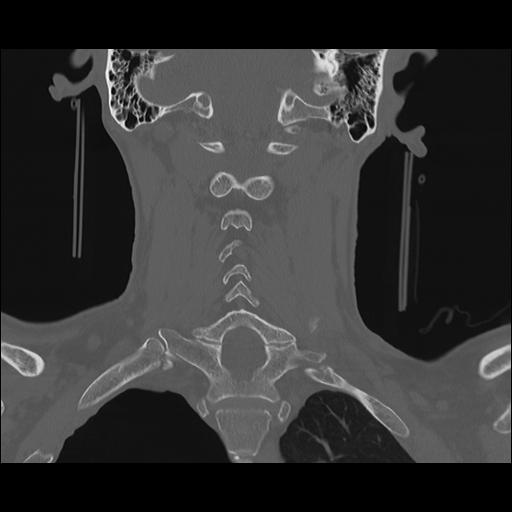

16 HUESO,,Coronal,2.000,HUESO,Coronal,